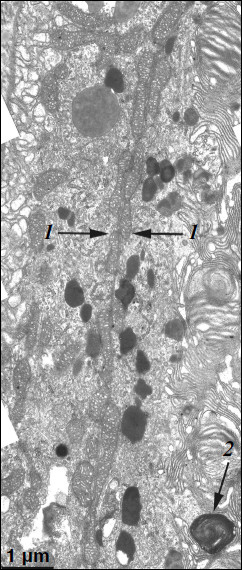

Ultrastructure of pigment epithelium cells. Pigment epithelium of Wistar cells (Fig. 1) consists of a layer of cells in the apical part of which there are fine strands of vertical extended cytoplasm offshoots surrounding rod outer segments. Phagosomes, debris of photoreceptor outer segments that underwent phagocytosis by pigment epithelium, sometimes can be seen in these cytoplasm offshoots near rod cell bases (Fig. 2). The characteristic ultrastructural feature of pigment epithelium is the presence in apical part of the cytoplasm of a layer of electron-dense structures (Fig. 1). As a rule, these structures are considered in the literature to be lipofuscin granules [12, 13]. We found in the apical part of pigment epithelium cells of 11-month-old Wistar rats practically continuous homogeneous layer of electron-dense structures – cytoplasmic inclusions (Fig. 1). Ultrastructural analysis of this layer showed that it contains morphologically extremely heterogeneous structures. First of all, these are lipofuscin granules. On the electron-microscopic photograph of the pigment epithelium region (Fig. 3a) arrows point to ultrastructure of two lipofuscin granules in the case of different section direction. It is seen that ultrastructure of lipofuscin granules corresponds to classical concepts. They can have round, oval, or polygonal shape depending on the section plane. Each granule is surrounded by a single-layer membrane contains moderately contrasting amorphous stroma substance (arrow 1) and aggregates of osmiophilic small granules (arrow 2). Oval osmiophobic regions or spherules (arrow 3) restricted by a layer of smallest particles of high electron density (arrow 4) can be seen within the amorphous substance. Besides, this layer of electron-dense structures includes large formations of variable size, shape, and internal arrangement. Figure 3b shows different structure of these formations. They are restricted by a single-layer membrane (arrow 1), contain granular stroma substance of different density in separate granules (for comparison arrows 2 and 3 point to granules of different density), and have heterogeneous ultrastructure along their length. Thus, arrow 4 in Fig. 3b points to a granule containing a region of fibrillar structure (arrow 5) as well as the close-type layers of concentric membranes restricting the space filled by the granular substance of electron density lower than that of stroma (arrow 6). We suppose that different ultrastructure of these formations is due to the fact that they are mutually transient structures, because various transient stages can be detected in their internal arrangement.

Figure 1

Fig. 1. Pigment epithelium region of 11-month-old Wistar rats. Arrows: 1) phagosomes; 2) the layer of electron-dense cytoplasmic inclusions; 3) mitochondria; N, cell nucleus.